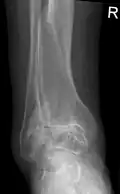

Diagnosis is made with reasonable certainty based on history and clinical examination.[52][53] X-rays may confirm the diagnosis. The typical changes seen on X-ray include: joint space narrowing, subchondral sclerosis (increased bone formation around the joint), subchondral cyst formation, and osteophytes.[54] Plain films may not correlate with the findings on physical examination or with the degree of pain.[55]

Severe osteoarthritis and osteopenia of the carpal joint and 1st carpometacarpal joint